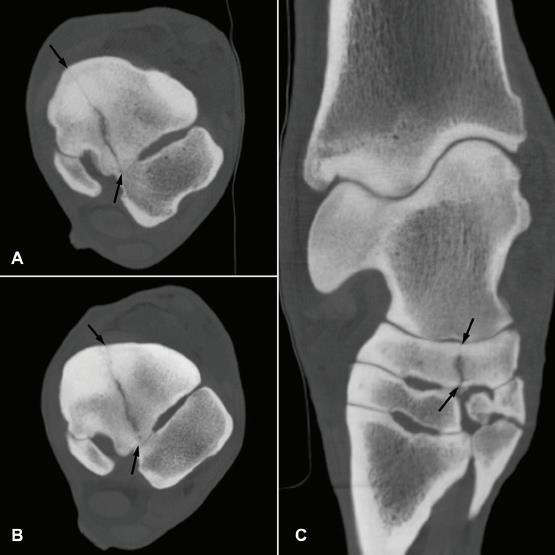

Variations of normal anatomy may be innocent but can in some cases be the tell-tale signs of developing pathology. Investigating such fi ndings with a combination of imaging techniques may prevent unfortunate consequences later. An example follows in Figures 12, 13, and 14.

Fig 12: Purchase examination image on the left and lameness examination image on right 6 months post-purchase that blocked to an abaxial sesamoid block. Area of sclerosis and region of subchondral injury of the sagittal groove of the proximal first phalanx which may be enhanced by a slightly flatter beam angle.

Fig 12: Purchase examination image on the left and lameness examination image on the right 6 months post-purchase that blocked to an abaxial sesamoid block. Area of sclerosis and region of subchondral injury of the sagittal groove of the proximal first phalanx (P1) which may be enhanced by a slightly flatter beam angle.

Figure 12: Purchase examination image on the left and lameness examination image on the right six months post-purchase that blocked to an abaxial sesamoid block. Area of sclerosis and region of subchondral injury of the sagittal groove of the proximal first phalanx (P1) which may be enhanced by a slightly flatter beam angle.

Image courtesy of Dr. Richard D. Mitchell.

Fig. 13: Nuclear scintigraphic image(left) showing focal zone of IRU on the proximal aspect of the left front first phalanx (P1) and corresponding dorsal plane MRI STIR image demonstrating subchondral osseous fluid associated with subchondral bone injury which was associated with an incomplete sagittal sulcus fracture.

Figure 13: Nuclear scintigraphic image (left) showing focal zone of IRU on the proximal aspect of the left front first phalanx (P1) and corresponding dorsal plane MRI STIR image demonstrating subchondral osseous fluid associated with subchondral bone injury which was associated with an incomplete sagittal sulcus fracture.